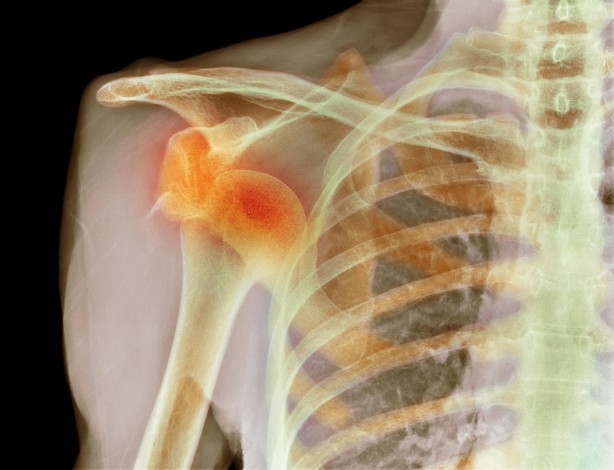

Gençlerde omuz çıkığı daha zor iyileşiyor

Omuz çıkığı şikayetlerinde en çok rastlanan yaşın 20’li yaşlar olduğuna değinen Prof. Dr. Cem Coşkun Avcı, “Omuz çıkığı çoğunlukla spor travmalarından sonra oluşuyor. Özellikle 20 yaş ve altında çıkığın tekrarlama ihtimali yüzde 95’lerdedir. Tekrarlayan Omuz çıkmalarını genellikle yüzerken ve gece yatarken yapılan normal aktiviteler sırasında da görüyoruz. Yüzme, futbol ve basketbol olarak bahsettiğimiz sportif aktiviteler çıkığın tekrarı için risk teşkil ediyor” dedi.

Ortopedi ve Travmatoloji Bölümünden Prof. Dr. Cem Coşkun Avcı, özellikle 20’li yaşlardaki gençlerde görülen omuz çıkığına ilişkin açıklamalarda bulundu. Prof. Dr. Cem Coşkun Avcı, omuz çıkığının oldukça ağrılı bir durum olduğunu belirterek, “Omuz çıkığı, omuz ekleminin eklem yuvasını terk etmesiyle oluşan bir durumdur. Böyle bir durumda omuzda şiddetli ağrı ile beraber şekil bozukluğu oluşuyor. Çoğunlukla hastalar omuzunun çıktığını fark ediyor. Omuz çıkığına en çok 20’li yaşlardaki gençlerde rastlıyoruz. Bu yaşlarda aktivite düzeyinin yüksek, dokuların elastikiyetinin fazla olması çıkığa yatkınlık oluşturur ancak her yaşta görülebilen bir durum. Yaşa göre tedavisi farklıdır” diye konuştu.

"YÜZÜCÜLER VE YOĞUN SPOR YAPANLAR RİSK ALTINDA" İnsan vücudunda en çok hareket eden eklemin omuz eklemi olduğuna değinen Prof. Dr. Avcı, şu şekilde devam etti: "Omuz eklemi vücudumuzun en hareketli yeri olduğundan dolayı en çok çıkan eklem olarak bilinir. Omuzu yerinde tutan kaslar, bağlar ve tendonlar vardır. Kişinin omzuna aldığı darbe veya ters hareket sonucu bu durum ortaya çıkabilir. Sportif aktiviteleri genellikle gençler yaptığı için omuz çıkmasını en çok onlarda görüyoruz. Özellikle kontakt spor olarak bilinen futbol, basketbol, hentbol ve voleybolla ilgilenenlerde omuz çıkığı riski daha yüksektir. Yüzücülerde de sık rastladığımız bir durumdur. İlk omuz çıkığında omzu uygun manevralarla yerine oturttuktan sonra bir kol askısıyla hastayı takip etmeye başlıyoruz. Çıkık esnasında omuzu yerinde tutan bağlar yırtılıyor. Yırtıklar omuz askısı takıldıktan sonra iyileşme dönemine giriyor. Omuz bağları yırtıldıktan sonra düzgün bir şekilde iyileşirse bir daha çıkık görülmez. Ancak bu iyileşme 20 yaş ve altındakilerde daha düşük orandadır. Bu yüzden genç hastada omuz çıkığı olmuşsa tekrarlama ihtimali yüzde 95’lerdedir. Tekrarlayan çıkıklarda cerrahi tedavi gerekiyor. İlk çıkık travmayla, darbeyle ve ters bir hareketle olurken tekrarlayan omuz çıkığı bu defa normal omuz hareketleri esnasında da oluşabiliyor. Bazen de belirgin bir çıkık olmadan omuz ağrısı ile kendini gösterebilir."

"KOL ASKISINDAN SONRA REHABİLİTASYON ŞART" Prof. Dr. Avcı, tedavide cerrahi yöntemlere başvurulan durumları şöyle açıkladı: "Sporcuların ilk çıkıklarından sonra da çoğunlukla cerrahi tedavi yapıyoruz. Tedavide kapalı yöntemle omzun yırtılan bağlarını yerine dikme işlemi yapıyoruz. Ameliyat sonrası omuzu kol askısına alıp yaklaşık 6 hafta bekliyoruz. 6 haftalık sürecin sonunda rehabilitasyon ile omuzu güçlendirme çalışmaları yapıyoruz. Omuz kas güçleri kazanıldıktan 3 ay sonra birçok aktiviteye izin veriyoruz. Ancak yüzme, futbol ve basketbol diye bahsettiğimiz sportif aktivitelere 6 aydan sonra izin veriyoruz. İyileşme süreci tamamlandıktan sonra kişi normal hayatına dönüyor. Bir omuz çıkığı oluştuktan sonra devamı da geliyorsa bunu engellemenin bir yolu kalmıyor. Omuz çıkığının artık devamlılığı söz konusu oluyor ve hastalarda da korku gelişiyor. Ya sporu terk ediyorlar ya da omuzu zorlayacak belli hareketleri hissettikleri için yapmamaya başlıyorlar. Zamanla hareket kısıtlılığına neden oluyor. Onun yerine çıkık tekrar ediyorsa cerrahi tedavi yapılması gerekiyor."